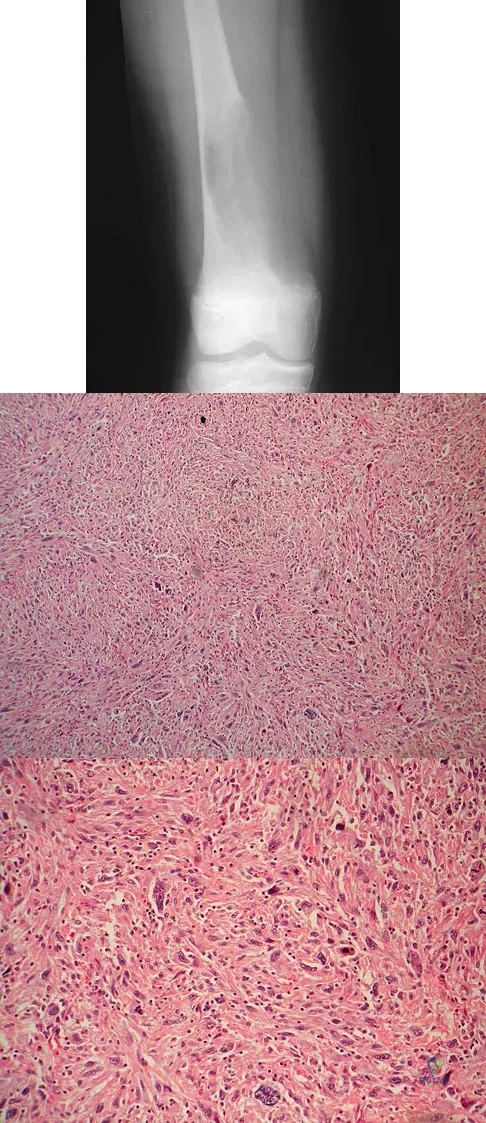

Question 86

A 12-year-old girl has had increasing left knee pain for the past 3 months. A radiograph is shown in Figure 75a, and low- and high-power photomicrographs are shown in Figures 75b and 75c. What is the most appropriate treatment?

Explanation